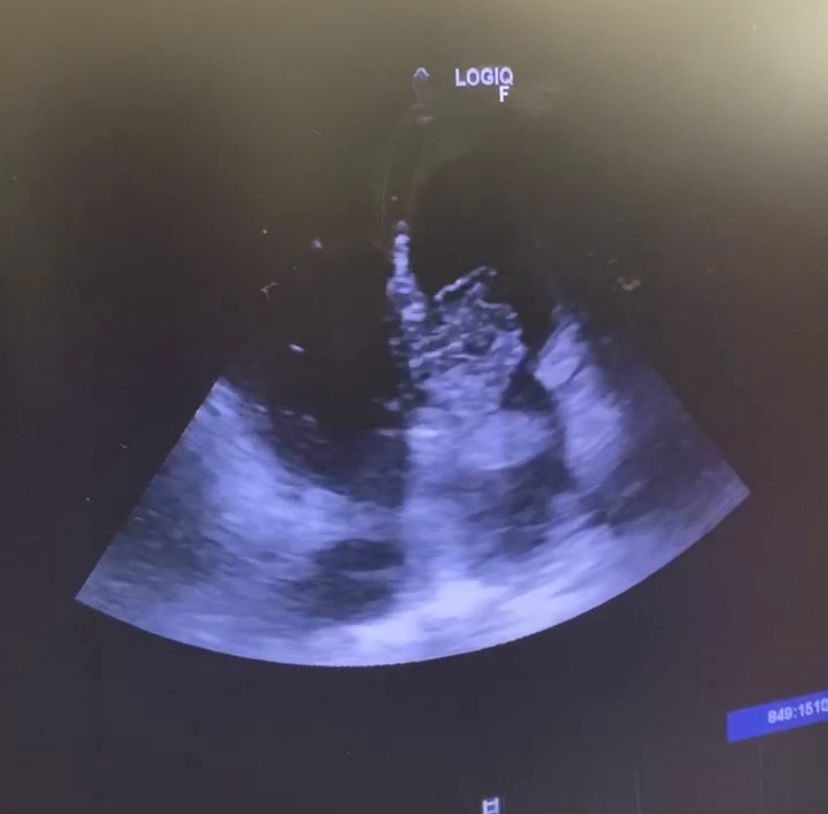

Se realiza ecografía trastorácica a pie de cama objetivándose gran masa a nivel de aurícula izquierda compatible con Mixoma auricular que protruye hacia válvula mitral generando obstrucción severa confirmándose en ecografía reglada posterior.

Juicio clínico: Mixoma auricular izquierdo de gran tamaño.

Diagnóstico diferencial: estenosis mitral.